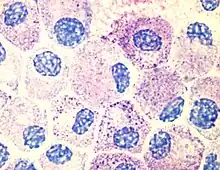

One of the most outstanding results of his dissertation investigations was the discovery of a new cell type. Ehrlich discovered in the protoplasm of supposed plasma cells a granulate which could be made visible with the help of an alkaline dye. He thought this granulate was a sign of good nourishment, and accordingly named these cells mast cells, (from the German word for an animal-fattening feed, Mast). This focus on chemistry was unusual for a medical dissertation. In it, Ehrlich presented the entire spectrum of known staining techniques and the chemistry of the pigments employed. While he was at the Charité, Ehrlich elaborated upon the differentiation of white blood cells according to their different granules. A precondition was a dry specimen technique, which he also developed. A drop of blood placed between two glass slides and heated over a Bunsen burner fixed the blood cells while still allowing them to be stained. Ehrlich used both alkaline and acid dyes, and also created new "neutral" dyes. For the first time this made it possible to differentiate the lymphocytes among the leucocytes (white blood cells). By studying their granulation he could distinguish between nongranular lymphocytes, mono- and poly-nuclear leucocytes, eosinophil granulocytes, and mast cells.